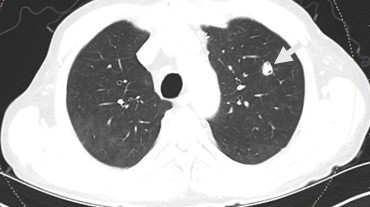

Case: A 65-year-old male patient with a history of kidney transplantation 10 years ago was admitted to outpatient clinic for erythema and edema on the dorsum of his left foot. He had no history of trauma. He was diagnosed with cellulitis due to leukocytosis and elevated CRP levels with his symptoms, and subsequently got oral antibiotic therapy. One week after the redness subsided, the discomfort intensified and CRP levels elevated further. Foot MRI has been performed and osteomyelitis in his fifth mettarsal bone has been investigated (figure 1). An MRI of the foot was conducted to evaluate osteomyelitis in the fifth metatarsal bone. Following a further 6 weeks of intravenous antibiotic treatment, a fistula developed, leading to a debridement surgery for sampling. Cryptococcus neoformans serotype A was isolated from bone tissue culture and treatment with fluconazole was initiated. A nodular lesion was observed in his chest CT scan despite the lack of respiratory symptoms (figure 2). There were no neurological symptoms or meningeal involvement observed in the cranial MRI, nevertheless, a lumbar puncture was conducted. A positive Cryptococcus neoformans latex agglutination test was detected in the cerebrospinal fluid analysis, requiring a change in his antifungal treatment to liposomal amphotericin B for disseminated disease involving central nervous system. During the same week, prostate imaging was conducted due to urinary retention, and an abscess was examined. Cryptococcus neoformans serotype A was cultured from the abscess after it was drained. Following a 4-week course of Liposomal amphotericin B treatment, antifungal medication was changed to fluconazole and continued for 12 months until full recovery and no complications or immune reconstitution inflammatory syndrome (IRIS) occurred, although a urinary tract infection developed during the therapy.